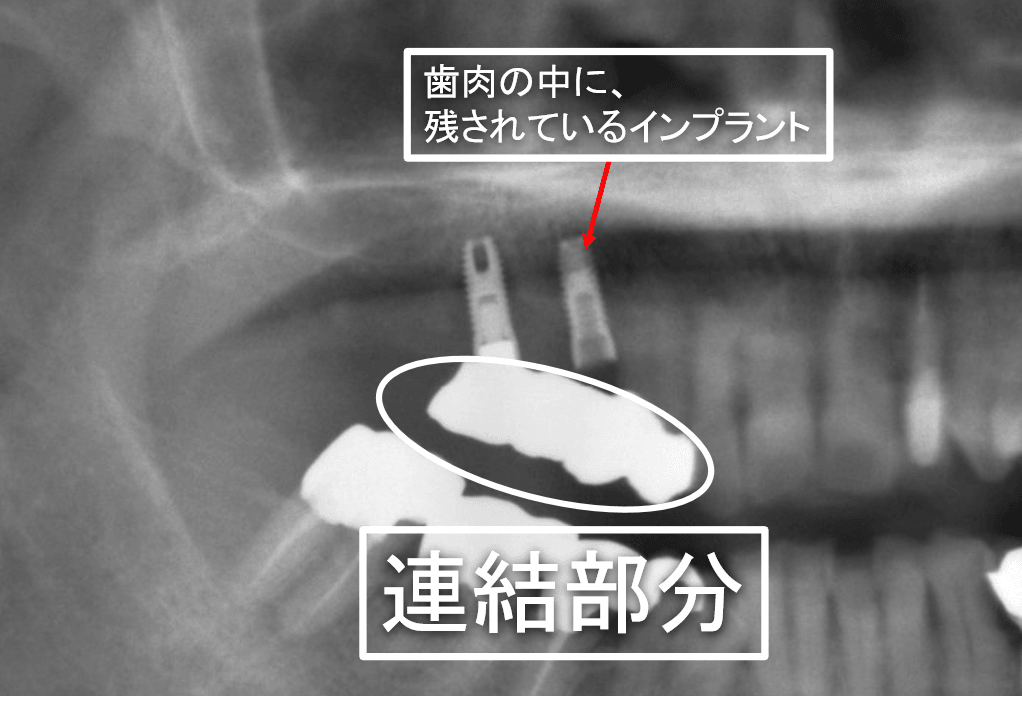

インプラントの2次オペ

こんんにちは。南館歯科クリニックの院長の木村です。 左下臼歯部のインプラントの症例です。 入れ歯を使用していましたが、どうしても抵抗があるということで、相談の結果、インプラントで治療を行…